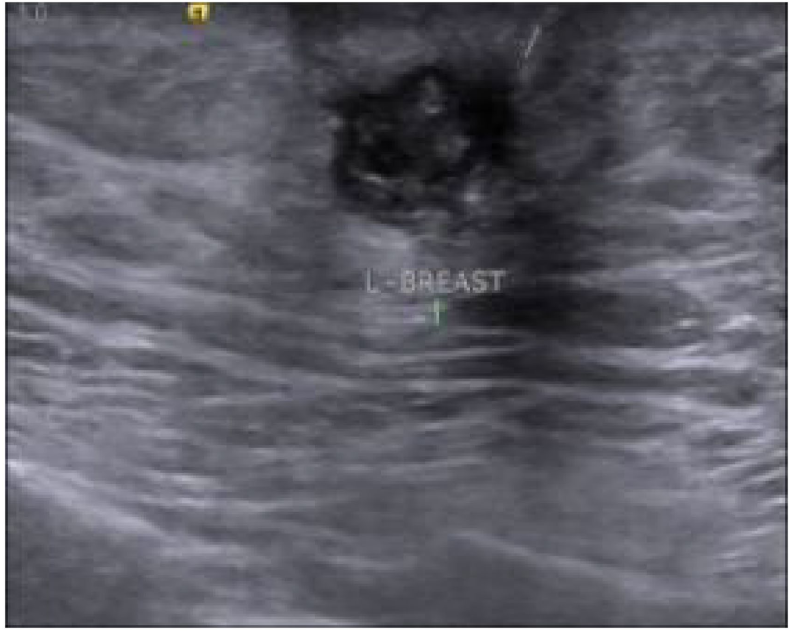

乳腺超声:左乳头根部可见 10×8mm 低回声肿块,边界不规则伴毛刺征,内部钙化,回声不均匀,BI-RADS 4C 类(图 1);

图1 左乳超声